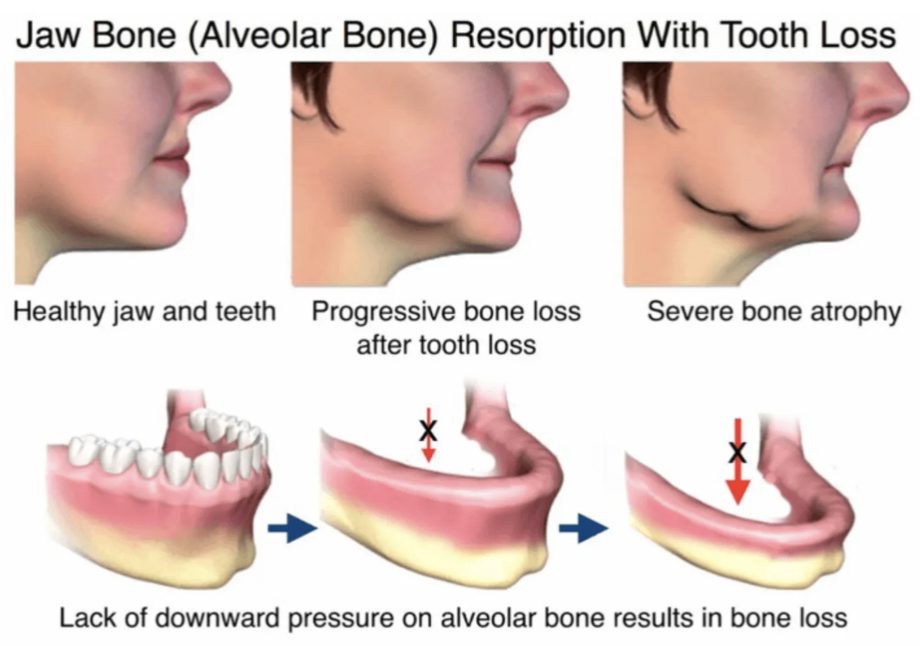

Dental implants are the only tooth replacement

option that prevents bone loss.

Missing tooth roots leads to long term bone loss. As the jaw(s) shrink, facial sagging, and advanced aging occur.

Dental implants are the only solution that stops this process. Traditional dentures and bridges fall short.

Dental implants are the only tooth replacement

option that prevents bone loss.

Missing tooth roots leads to long term bone loss. As the jaw(s) shrink, facial sagging, and advanced aging occur. Dental implants are the only solution that stops this process. Traditional dentures and bridges fall short.